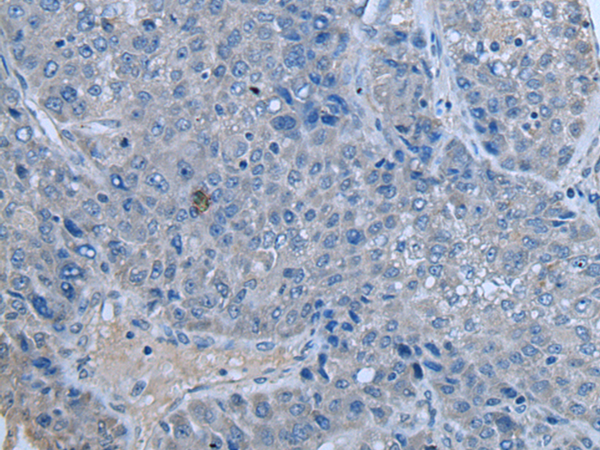

分类: 科研抗体货号: P12820别名: CENF; hcp-1; CILD31; PRO1779应用: IHC反应种属: Human

分类: 科研抗体货号: P12837别名: ZAP; ZC3H2; ARTD13; PARP13; FLB6421; ZC3HDC2应用: IHC反应种属: Human

分类: 科研抗体货号: P12836别名: C19orf7应用: IHC反应种属: Human, Mouse

分类: 科研抗体货号: P12818别名: ATG1; ATG1A; UNC51; hATG1; Unc51.1应用: IHC反应种属: Human

分类: 科研抗体货号: P12835别名: ZNF923应用: IHC反应种属: Human